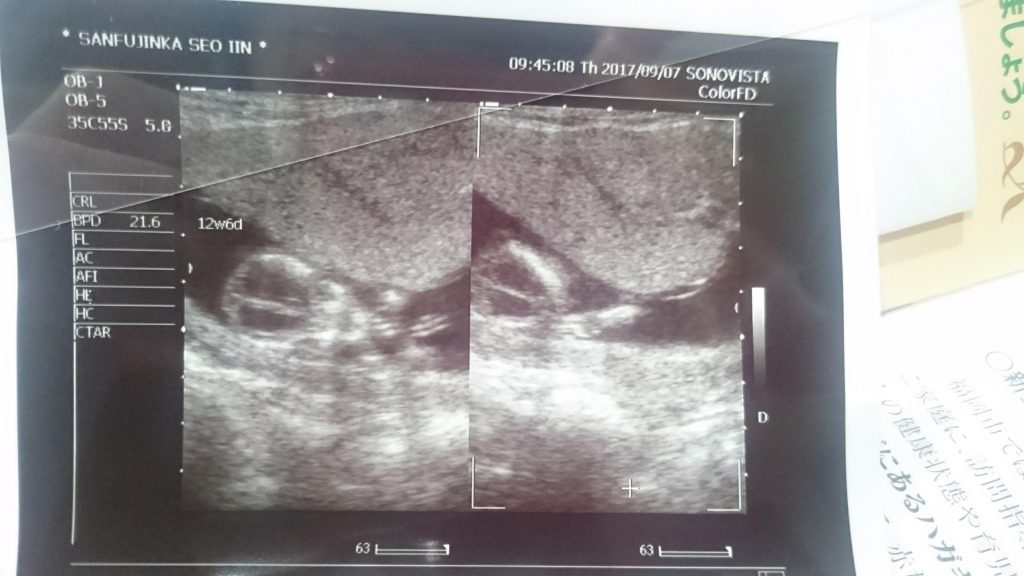

トツキトオカのアプリをみながら、この9カ月を振り返ってみました。

2017年7月。脳貧血で倒れることが2回あり、妊娠が発覚。

つわりと情緒不安定で、めちゃくちゃしんどかった。廃人状態。。。

8月。福岡の家族に報告した。31歳の誕生日を迎えた。

9月。大阪で入籍。やっと安定期を迎え、中央アジアの旅も出来た。